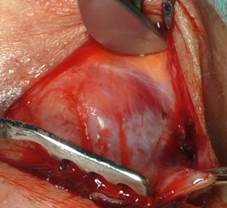

Объем хирургического вмешательства у пациентов с птозом определяли по данным интраоперационного состояния анатомических структур верхнего века. Все операции были выполнены под местной анестезией транскутанным доступом. После проведения разреза по пальпебральной складке обнажали верхний край тарзальной пластинки, после чего проводили визуальный анализ состоятельности дистальной части апоневроза леватора. В случае если апоневроз был изменен и истончен (рис. 1), то в первую очередь выполняли его дубликатуру с последующей оценкой уровня верхнего века в положении пациента сидя. Если эффект был недостаточный, то проводили вскрытие тарзоорбитальной фасции и фиксацию плотной части апоневроза к верхнему краю тарзальной пластинки (рис. 2). В случаях, когда апоневроз леватора не был визуально изменен, мышцу Мюллера ножницами отделяли от апоневроза (рис. 3) и выполняли ее резекцию с последующим гистологическим исследованием.

Рис. 1. Истончение апоневроза леватора

Источник: составлено авторами по результатам данного исследования.